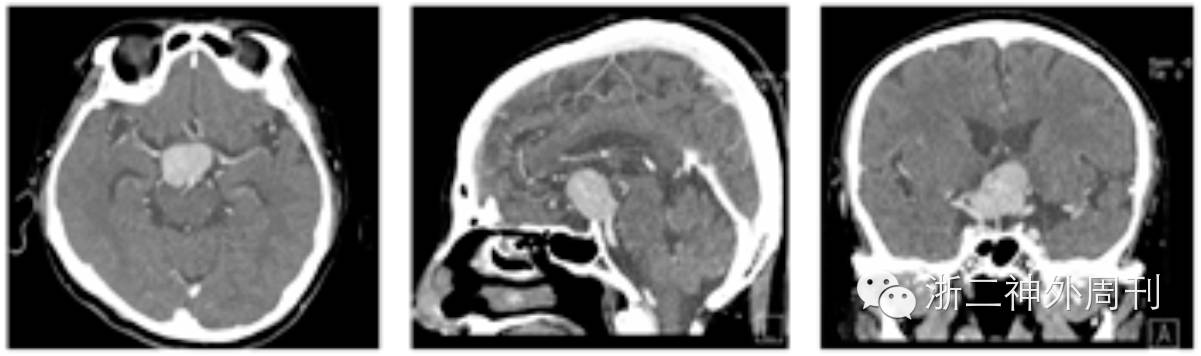

行CT检查发现平扫未见钙化,肿瘤有强化(图3)。

图3. CT检查:未见钙化,肿瘤较均匀增强。